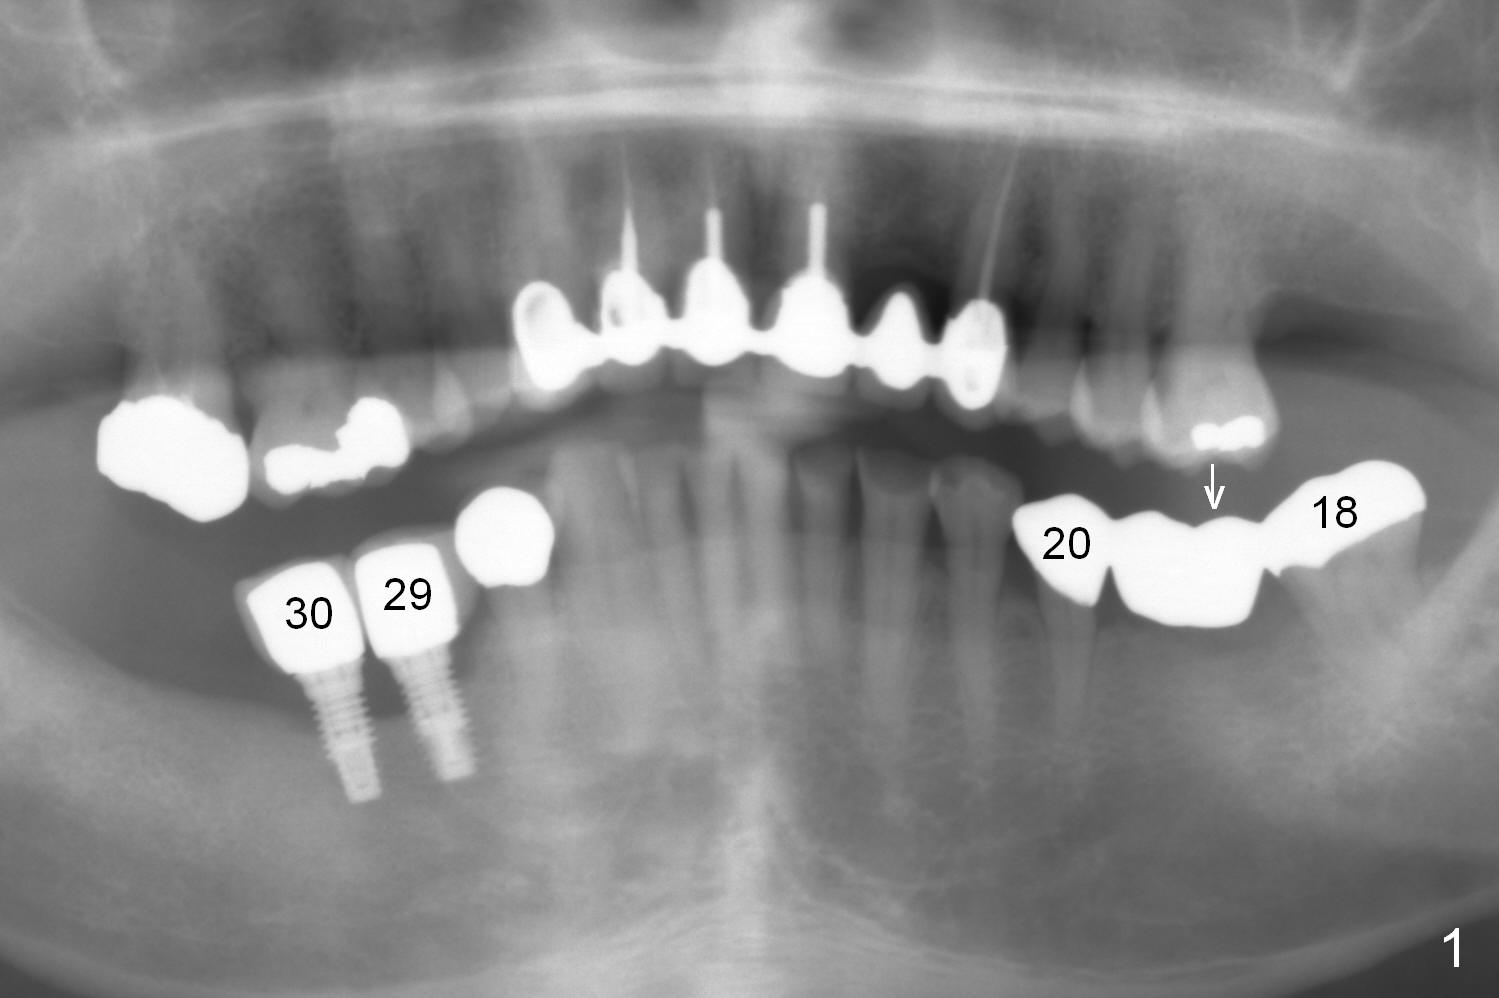

A 71-year-old man has lost an implant at #29 (Fig.1 (taken 3 years earlier)). CT shows that the implant at #30 is failing. The biggest challenge of re-placing implants at the lower right is lack of keratinized gingiva. Gingival graft is mandatory.

The abutment tooth at #18 is symptomatic with gingival recession (Fig.2). It appears that it is overloaded due to pressure from the tooth #14 (Fig.1 arrow). An implant at #19 should be able to alleviate the pressure on the tooth #18.

The 3-unit bridge (#18-20 in Fig.1) will be sectioned (Fig.2 red lines) with the pontic of #19 to be removed. The ridge top is narrow (Fig.3). To place a 5 mm UF implant, the triangular ridge top should be reduced (result).